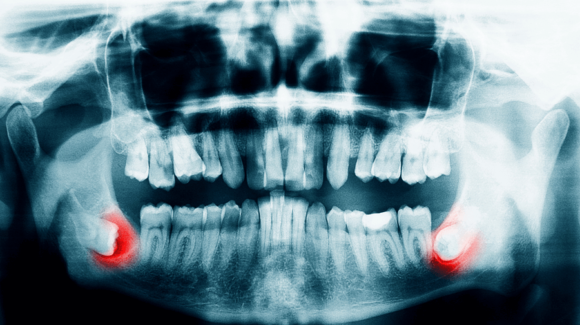

Bölcsességfog gyulladás – tünetek, otthoni teendők, kezelés

Evolúciós szempontból a legtöbb bölcsességfog már inkább csak valamilyen csökevénynek mondható, hiszen sem alakját, sem méretét tekintve nem tudná eredeti funkcióját betölteni. Többeknek már a fog csírája is hiányzik, akiknek meg van, azok többsége meg is tapasztalja, hogy milyen egy bölcsességfog gyulladás. Manapság sajnos már az a ritka, ha valakinek nem okoz gondot a leghátsó, legutolsó fog.

A szájsebészet területén rutin beavatkozásnak számít a bölcsességfog kezelése, a fogorvosok többsége pedig egyetért abban, hogy nem igazán éri meg a megmentésére energiát és pénzt áldozni. Jobb mihamarabb eltávolítani őket, nélkülük ugyanis sokkal könnyebb fenntartani a jó szájhigiéniát.

A bölcsességfog gyulladás okai:

• Ha a felette lévő csontréteg miatt nem tud előtörni

• Ha nincs elég hely vagy nem egyenesen nő vagy a szomszéd fogba ütközik az előtörése során

• Ha ciszta alakul ki körülötte

• Ha a nehéz tisztítása miatt elromlik, kilyukad

• Ha a felhalmozódott lepedék, fogkő miatt ínytasak képződött körülötte